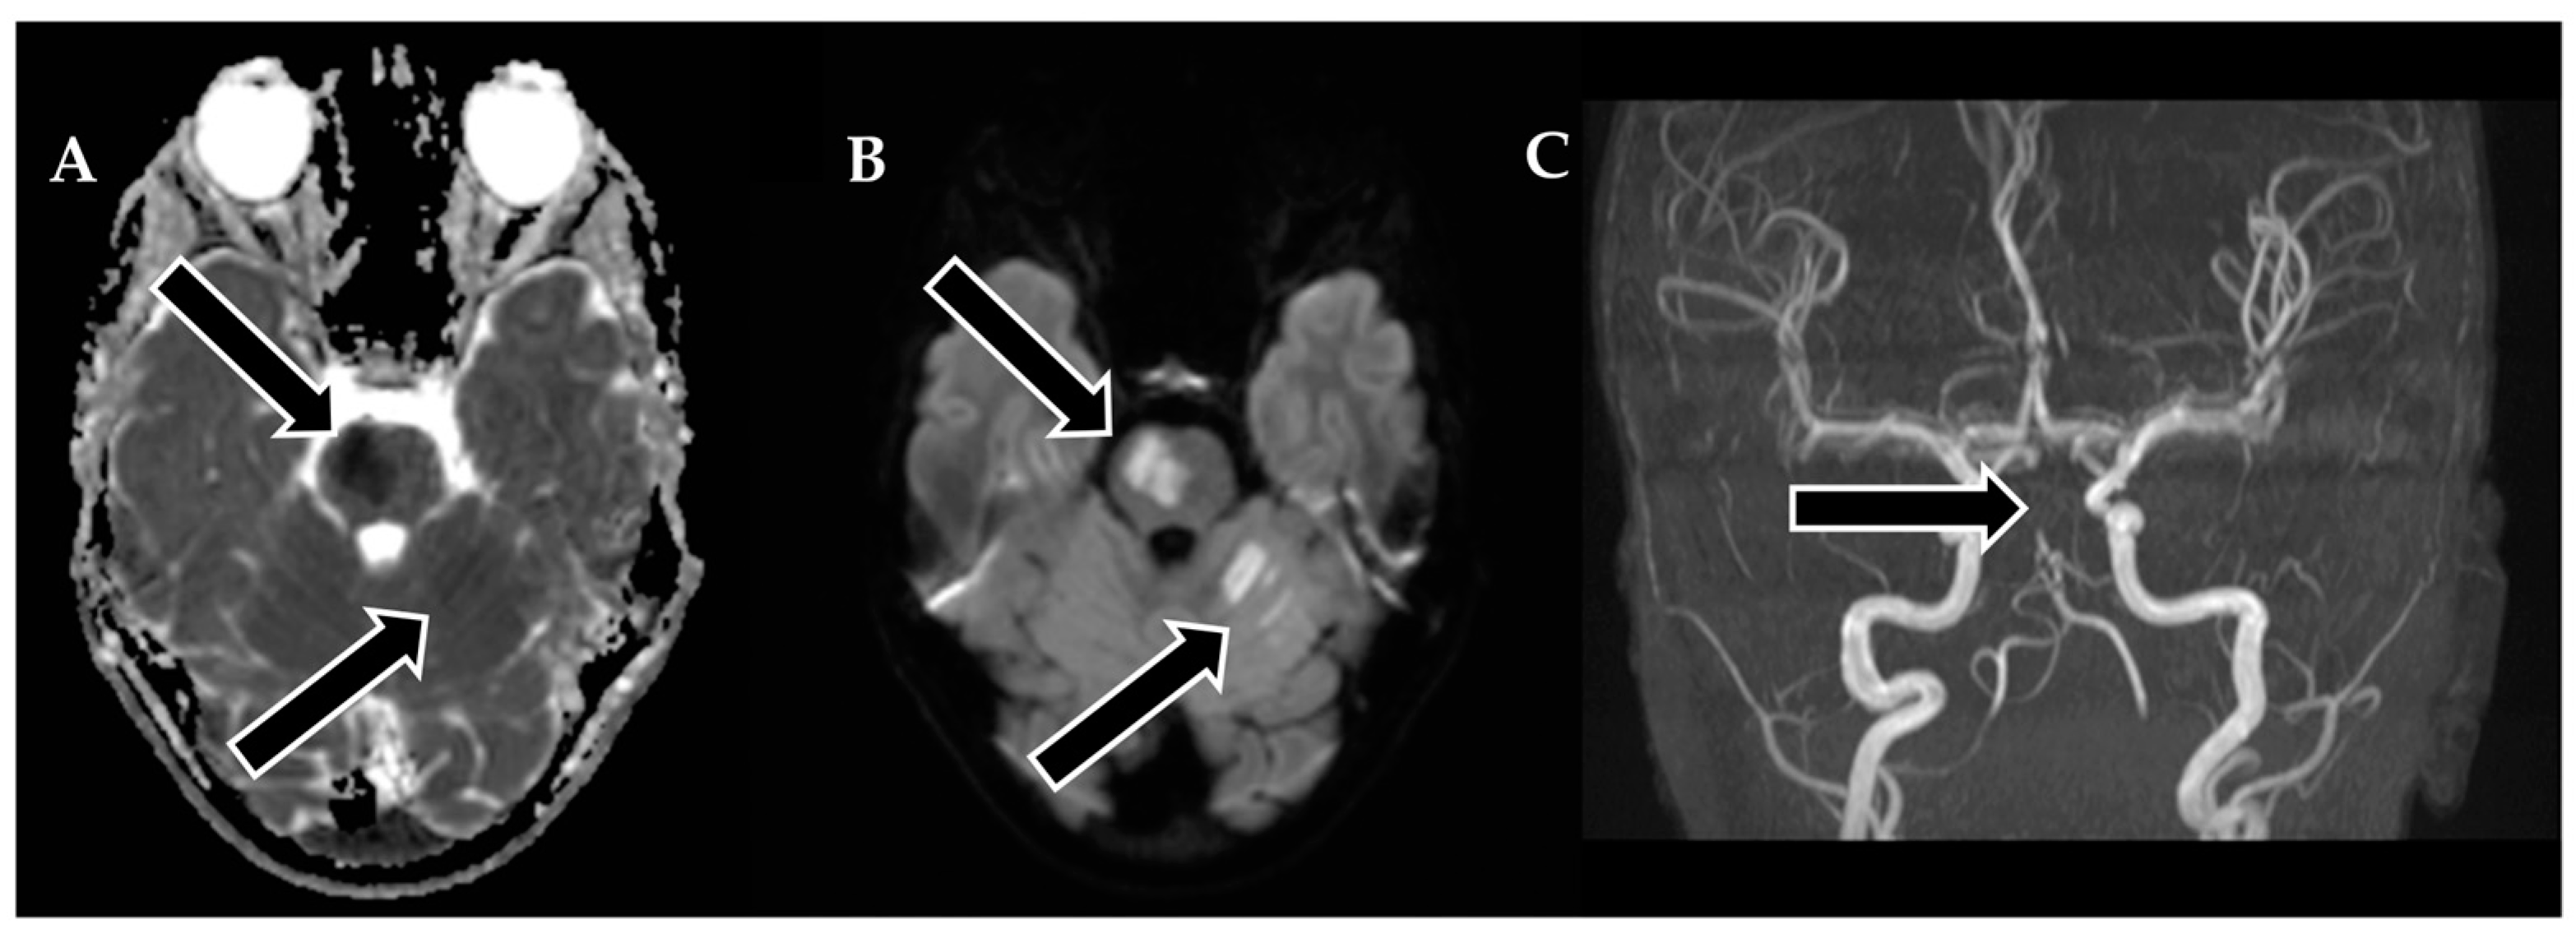

To restore normal blood flow to the affected areas, an aspiration catheter known as “Sofia” (Terumo, Tokyo, Japan) was carefully positioned in the distal V2 segment. Throughout the procedure, multiple left vertebral arteriograms were performed, consistently illustrating blockages in the middle segment of the basilar artery. After six meticulous attempts, a final angiogram conclusively confirmed the complete removal of the obstructions in both the basilar artery and the posterior cerebral arteries, achieving a TICI scale score of 3, indicating full and successful revascularization (Figure 3).

Figure 3. Neurointerventional procedure. (A,B) Initial angiogram from anterior–posterior and lateral views reveals an upper third basilar artery occlusion and no enhancement in both posterior cerebral arteries (TICI scale: 0). (C,D) After the first attempt, angiogram views show improved basilar artery enhancement, but filling defects and absent enhancement persist in both posterior cerebral arteries. (E,F) Post-thrombectomy angiograms demonstrate enhanced perfusion in the basilar artery and both posterior cerebral arteries (TICI scale: 3).